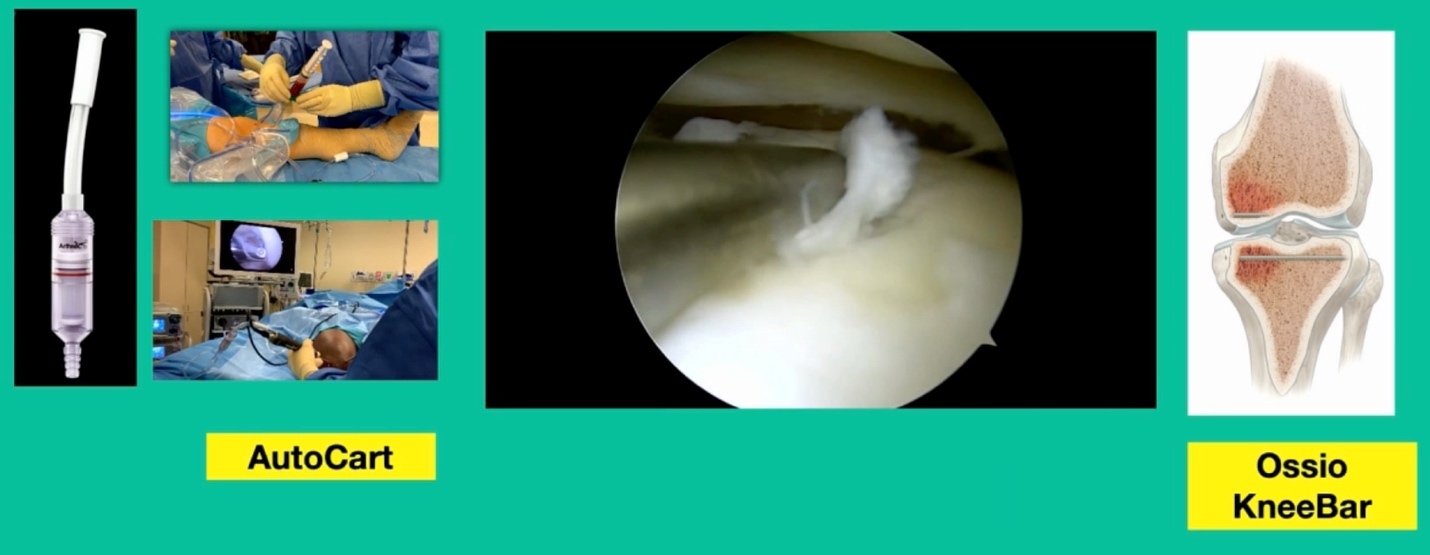

This is another one. 38-year-old, lateral side knee pain, lots of edema.

What’s amazing with this one is he’s got that little focal defect, but tremendous edema there and lots of bone pain. This one, we did something called AutoCart™ (Arthrex, Inc.).

Now, it’s an interesting procedure, and it’s sort of a poor person’s cartilage transplant. We take advantage of the body’s innate ability to heal. That’s the lateral tibial plateau and we’re curating the base of it. Using a shaver we grab cartilage from the intercondylar notch and we collect it in a little receptacle (that’s collecting the cartilage).

We then make this sort of “witches’ brew” of articular cartilage, which is living articular cartilage, some collagen, what we call bio cartilage as a scaffold, and bone marrow concentrate, and then we create a paste. Then, arthroscopically, we introduce it, and we put fibrin glue over it. Then, to treat the edema, we do something called OssioFix or KneeBar (Ossio Inc.) where we take a biocomposite pin. It’s like a rafter screw, and we put it across the tibia to shore up the tibia. We have now about 20 patients who have been treated this way and it can be very good because we’re treating the bone and the cartilage.